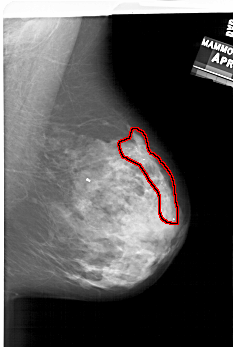

FILE: A_2000_1.RIGHT_CC.OVERLAY

TOTAL_ABNORMALITIES 1

ABNORMALITY 1

LESION_TYPE CALCIFICATION TYPE PLEOMORPHIC DISTRIBUTION SEGMENTAL

ASSESSMENT 4

SUBTLETY 4

PATHOLOGY MALIGNANT

TOTAL_OUTLINES 1

BOUNDARY